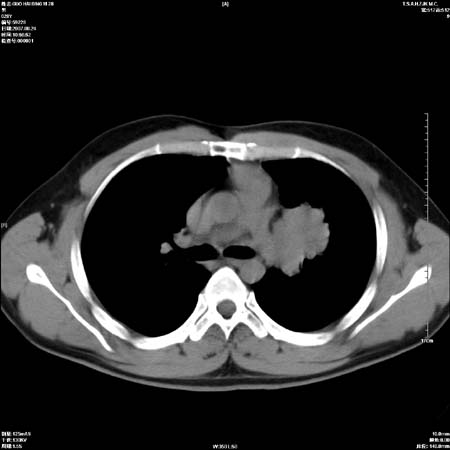

左肺门区软组织肿块,左肺上叶支气管开口消失,纵隔内见肿大淋巴结,考虑左中心型肺部,可以做纤支镜取病理确认.

左肺肺门区肿块影,分叶明显,左肺上叶支气管开口受压,纵隔内见肿大淋巴结,考虑左中心型肺癌。

支持左上叶中央型肺癌伴纵隔淋巴结转移.

左上叶中央型肺癌伴纵隔淋巴结转移

肿块形态影像支持左上叶中央型肺癌伴纵隔淋巴结转移。

左肺门区分叶状软组织肿块,纵隔内有肿大淋巴结,诊断肺癌应该问题不大。

直接下肺癌诊断还太早,病灶较大,估计5cm以上,但阻塞性改变及对临近纵隔及支气管侵犯不明显,密度较均匀,弓旁见一单个淋巴结,需要排除炎症性肿块及腺瘤,平滑肌瘤等。